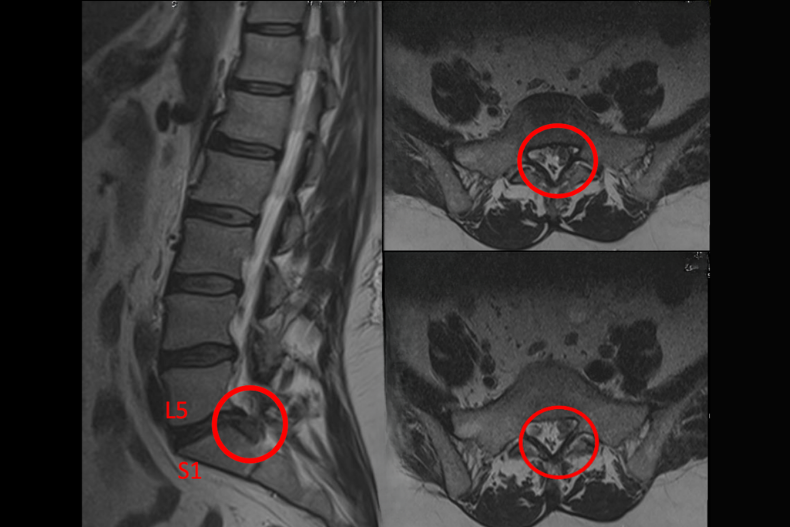

L5-S1 bel fıtığı, omurganın en alt kısmında yer alan L5 omuru ile sakrum (S1) arasındaki disk yapısının bozulmasıyla ortaya çıkar. Bu bölge, omurganın taşıdığı yükün ve hareketin en yoğun olduğu kısım olduğu için bel fıtığının en sık görüldüğü seviyedir. Günlük yaşamda ağır kaldırma, uzun süreli oturma ya da yanlış hareketler sonucu bu bölgede disk yırtılması meydana gelir ve sinir köklerine baskı oluşur.